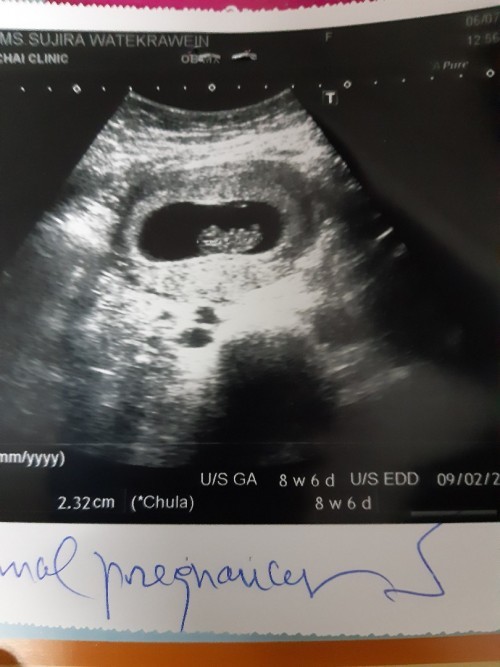

อันนี้ตอน8w6วันค่ะ